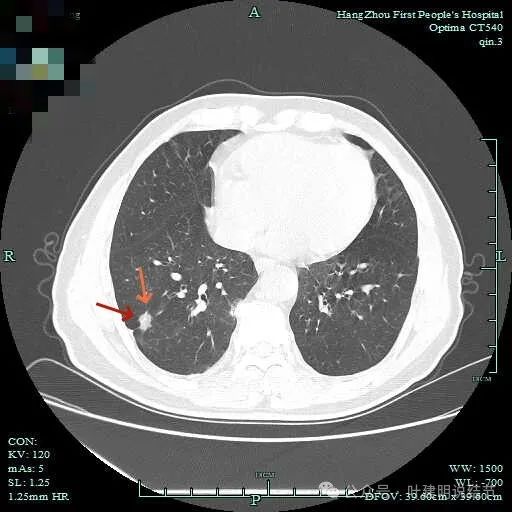

上图呈结节状,表面不平,有少许磨玻璃成分。

结节状,密度高,边缘欠光滑。

与脊柱之间有间隙,表面有细毛刺。

表面不平,似有细支气管截断征。

边缘不平毛糙。